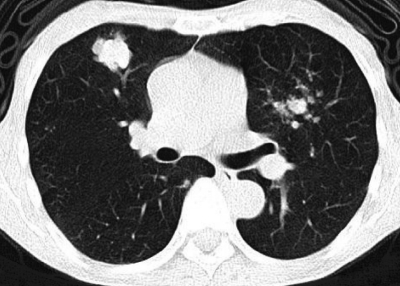

尿所見:蛋白(-)、糖(-)、沈渣に赤血球1〜5/1視野、白血球1〜5/1視野。血液所見:赤血球 420 万、Hb 12.8 g/dL、Ht 41 %、白血球 3,900、血小板 17 万。血液生化学所見:総蛋白 7.0 g/dL、アルブミン 3.8 g/dL、総ビリルビン 1.1 mg/dL、AST 34 U/L、ALT 36 U/L、LD 176 U/L(基準 176〜353)、γ-GTP 38 U/L(基準8〜50)、 尿素窒素 20 mg/dL、クレアチニン 1.0 mg/dL、尿酸 7.1 mg/dL、血糖 96 mg/dL、Na 137 mEq/L、K3.9 mEq/L、Cl 104 mEq/L。CRP 0.1 mg/dL。心電図に異常を認めない。11 か月前と今回の胸部CTを示す。

今回